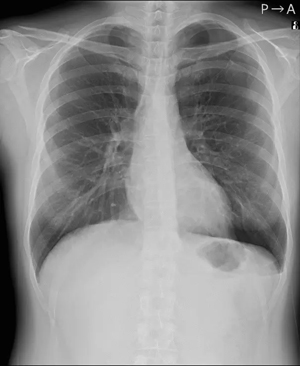

気胸とは、何らかの原因で肺に穴が開き、肺がしぼんでしまう状態を指す。胸の痛み、咳、息切れや呼吸困難などの症状を伴うことがあり、緊張性気胸に進展した場合には生命に危険が及ぶ可能性がある。そのため、早期発見・診断が重要であるが、胸部単純X線画像撮影の主目的が気胸の確認ではない場合は見落とされるリスクが高い所見でもある。

「CXR Finding-i 気胸検出タイプ」は、胸部単純X線画像をAI※2で解析することで重要所見である気胸の候補を迅速に検出し、候補領域を画像上に表示することで見落とし防止を支援する。病変検出性能を示す指標である感度※3は95%と高い水準を実現していることに加え、気胸が存在しない画像をAIが正しく陰性(気胸なし)と判断した割合を示す特異度※4は96%であり、病変を見逃さないようにしつつ偽陽性も抑制した高精度の検出性能が特長である。

気胸が存在すると診断された異常例87症例、対照例213症例の胸部単純X線画像を対象に行った読影試験に対する本製品の単体性能は以下の通りである。

| 検出可能病変 | 気胸 |

| 感度 | 95% |

| 特異度 | 96% |